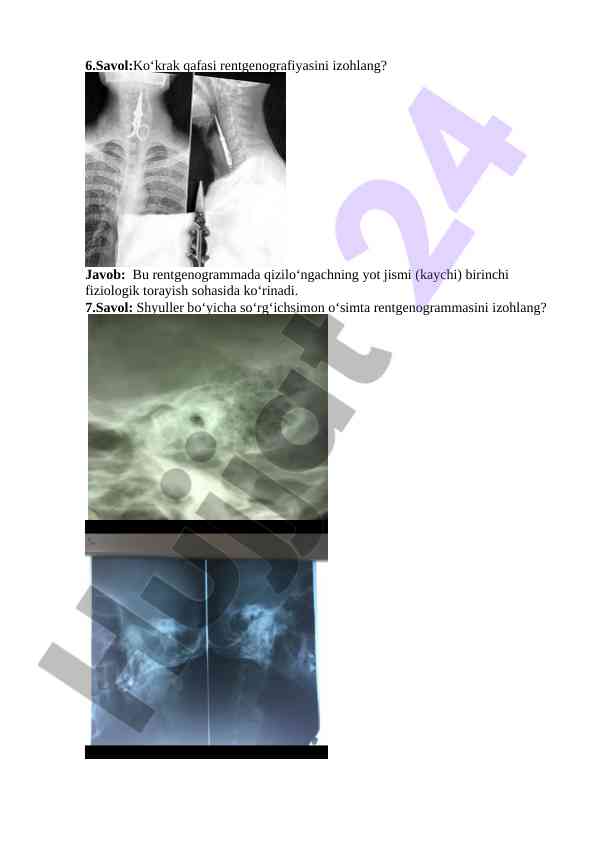

Rentgenografiya bo‘yicha savollar va javoblar, burun yon va ko‘krak qafasining rentgenogrammalarini tahlil qilish. O‘quv jarayoni uchun zarur ma'lumotlar va tahlil mezonlari.